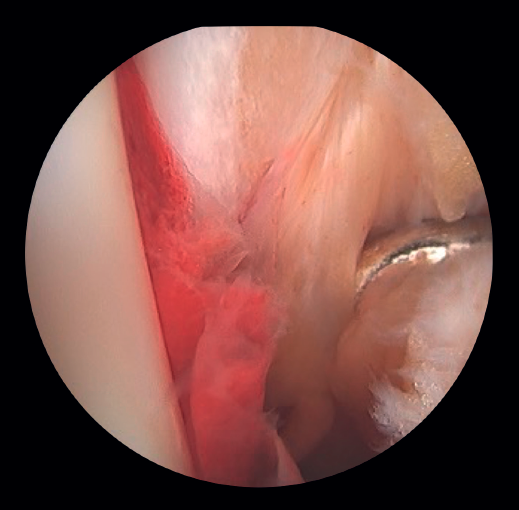

- Diagnosis of syndesmotic instability. Arthroscopy allows assessment of the integrity of the syndesmosis and the MCS on the radiograph and CT scan, especially in SER II and IV fractures. It has been shown that radiographic assessment is not always predictive of the syndesmotic lesion. In addition, arthroscopy ensures its anatomical reduction. Takao found that 87% (33/38) of the ankles with fractures had syndesmosis lesions detected by arthroscopy(20).

Arthroscopy allows both direct visualization and dynamic assessment of the syndesmosis(21,22).

- It makes it possible to differentiate between SER II fractures (where there should be no syndesmosis damage) and SER IV fractures, where the syndesmosis is affected and can be stabilized(5,23).

- Arthroscopy can avoid the false impression of a widened medial joint space on fluoroscopy due to congenital anomalies.

- Being able to visualize the malleolar incisura together with radioscopic control allows us to ensure correct positioning of the incisura fibularis, especially in patients with unstable injuries where there is a risk of malreduction due to shortening or rotation of the fibula(5,24).

- Arthroscopy can help avoid overcorrection of the syndesmosis, which is highly arthrogenic(5,24)(Figure 6).